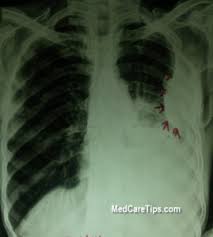

Pleural effusion (basic) large unilateral pleural effusion; Ultrasound findings are relevant for pleural infection as in heavily septated or loculated effusions, the biochemical results can be different in the discrete areas, so can give falsely reassuring results. Cardiac ct and mri scans: Pneumonia) and loculated effusions from free fluid in the pleural space. When this is the case a chest tube may only drain that collection of fluid in the area where the chest tube is placed. To a great extent, the outlook for patients with pleural effusion depends on the primary cause of effusion and whether it can be eliminated. The latter are more likely to change with patient positioning 12. Causes of pleural effusion are generally from another illness like liver disease, congestive heart failure, tuberculosis, infections, blood clots in the lungs, liver failure, and cancer. Loculated effusion) or underlying atelectasis. Strange or atypical configurations of pleural fluid can be due to either adhesions (i.e. B, pleural fluid within a locule; Feb 07, 2020 · learn about pleural effusion (fluid in the lung) symptoms like shortness of breath and chest pain. If your doctor suspects a malignant pleural effusion, the next step is usually a thoracentesis, a procedure in which a needle is inserted through the chest wall into the pleural space to get a sample of the fluid.

B, pleural fluid within a locule; If your doctor suspects a malignant pleural effusion, the next step is usually a thoracentesis, a procedure in which a needle is inserted through the chest wall into the pleural space to get a sample of the fluid. Useful for differentiating pleural effusions from consolidation (e.g. Strange or atypical configurations of pleural fluid can be due to either adhesions (i.e. Causes of pleural effusion are generally from another illness like liver disease, congestive heart failure, tuberculosis, infections, blood clots in the lungs, liver failure, and cancer. Cardiac ct and mri scans: Jan 04, 2020 · poor tube placement (some pleural effusions are loculated, in other words, have several small collections of water, pus, or blood, which is separated by tissue. Whenever a large effusion causes a patient to be short of breath, thoracentesis will make breathing easier, and it may be repeated if necessary. Pleural effusion (basic) large unilateral pleural effusion; Loculated effusion) or underlying atelectasis. Pneumonia) and loculated effusions from free fluid in the pleural space. When this is the case a chest tube may only drain that collection of fluid in the area where the chest tube is placed. In patients with symptomatic malignant pleural effusions with nonexpandable lung, failed pleurodesis, or loculated effusion, we suggest the use of ipcs over chemical pleurodesis.